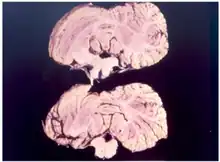

Kuru is a rare, incurable, and fatal neurodegenerative disorder that was formerly common among the Fore people of Papua New Guinea. Kuru is a form of transmissible spongiform encephalopathy (TSE) caused by the transmission of abnormally folded proteins (prions), which leads to symptoms such as tremors and loss of coordination from neurodegeneration.

Kuru, a transmissible spongiform encephalopathy, is a disease of the nervous system that causes physiological and neurological effects which ultimately lead to death. It is characterized by progressive cerebellar ataxia, or loss of coordination and control over muscle movements.[11][12]